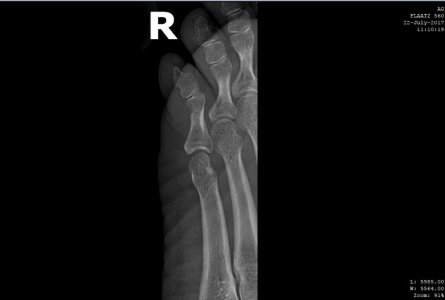

Здравствуйте! Прошу помощи. Прошло 18 дней со дня перелома мизинца (4 июля), к сожалению,находясь заграницей так и не удалось попасть к нормальному врачу, ходила с примотанным пластырем к соседнему пальцу, синяк почти прошел, сегодня сделали снимки - по -моему разницы никакой, угол отломка не изменился, при опоре на мизинец чувствуется давление и распирание внутри, будто эта кость торчит там внутри что-ли, как мешает что-то, при опоре отъезжает и смотрит немного в сторону, расстояние с соседним пальцем больше, чем на здоровой ноге. Думаю насчет возврата на родину и лечения в Москве. Вопрос - можно и нужно ли его еще как-то вправить, какой предельный срок? Не станет ли хуже от этих правок?

Забыть и ходить как есть? Какие последствия если не так срастется? Дискомфорт при ходьбе будет? Для меня это очень важно, заранее благодарю за ответ. Первый снимок - сразу после перелома 4 июля, остальные - 22 июля.